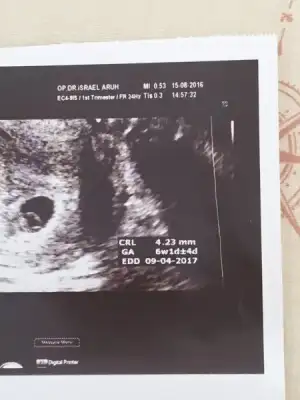

Canım bi de en az 6 haftalık olması lazım senin daha erken sanırım. Ben ilk gittiğimde soldaydı sonradan sağa geçti 6 ve 7. haftalarda hep sağda duruyor. Seninki kaç haftalık bu usgdeTamam çekerim canım bu vajinal usg